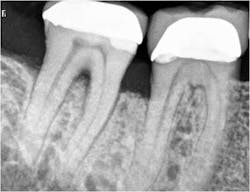

• The use of biologic modifier such as PDGF-BB as an adjunct to bone particulate and collagen membranes

In the present case, a 61-year-old male was referred to my periodontal office by his general dentist for an evaluation of pain and bleeding to the lower right mandible. The patient’s medical history consisted of controlled type 2 (noninsulin dependent) diabetes and hypertension. Upon review of the panoramic radiograph (figure 1), the periodontal defects are not clearly evident, thus showing the importance of proper radiographs to detect periodontal defects. The periapical radiographs (figure 2) clearly show subgingival calculus, grade 1 furcation on No. 30, grade 3 furcation on No. 31, and an advanced intrabony defect on the distal of No. 30. Clinically, there was no mobility to either No. 30 or 31 and both teeth were vital. Tooth vitality is an extremely important diagnostic factor in treatment panning. Periodontal charting of the lower right was also performed, and the lower right exhibited bleeding and inflammation (figure 3).